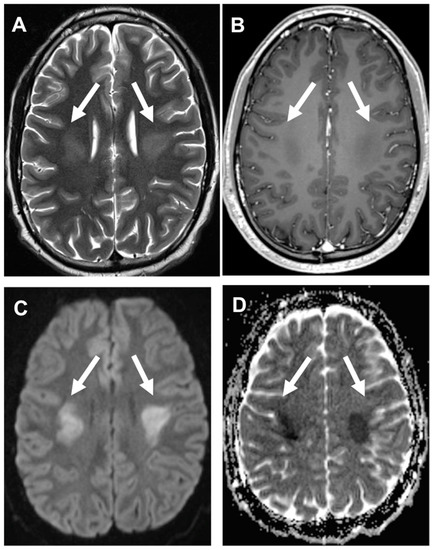

3.4. Acute Late-Onset Encephalopathy after Radiotherapy (ALERT Syndrome)

- Di Stefano, A.L.; Berzero, G.; Vitali, P.; Galimberti, C.A.; Ducray, F.; Ceroni, M.; Bastianello, S.; Colombo, A.A.; Simoncelli, A.; Brunelli, M.C.; et al. Acute late-onset encephalopathy after radiotherapy: An unusual life-threatening complication. Neurology 2013, 81, 1014–1017. [Google Scholar] [CrossRef] [PubMed]

- Ito, H.; Mori, K.; Kagami, S. Neuroimaging of stroke-like episodes in MELAS. Brain Dev. 2011, 33, 283–288. [Google Scholar] [CrossRef] [PubMed]